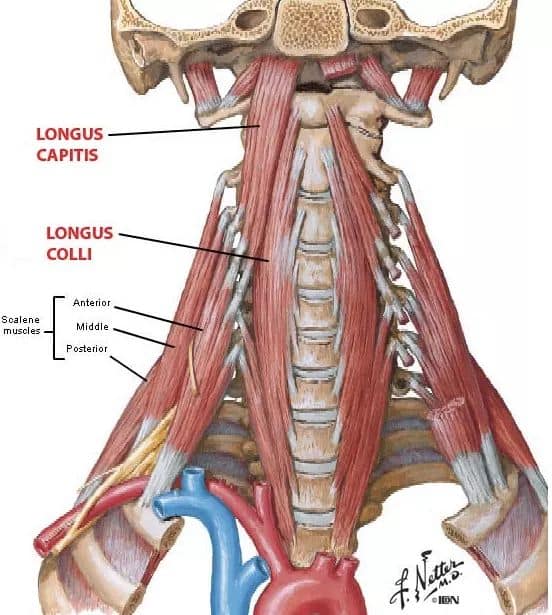

Шийні м'язи

Шийні м'язи мають важливе значення для підтримки голови і забезпечення її рухів.

М'язи передньої групи

М'язи, що згинають шию: М'язи, що згинають голову (м'язи передньої групи): виконують рухи, які дозволяють опускати і піднімати голову.

М'язи бічної групи

М'язи, що повертають голову: Стерноклейдомастоїдний м'яз: один з найважливіших м'язів, який дозволяє здійснювати повороти і нахили голови. Він походить від грудини та ключиці і прикріплюється до соскоподібного відростка скроневої кістки.

М'язи задньої групи

М'язи, що розширюють шию: М'язи, що розширюють шию: включають трапецієподібний м'яз, який бере участь у піднятті плечей і розширенні шиї.